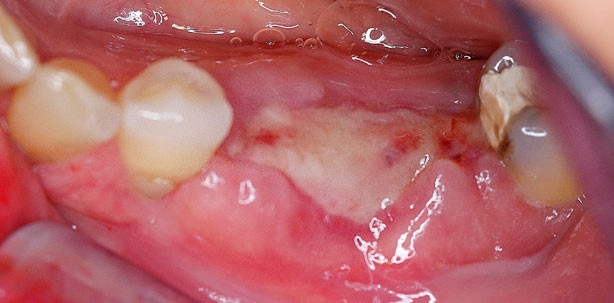

Foto: © Dr. Y. Zubery

Frühe Wund-Dehiszenzen führen häufig zu einer Infektion des Augmentats und/oder zu einem kompromittierten Behandlungsergebnis. Dies ist zumeist auch bei der zusätzlichen Verwendung einer handelsüblichen Kollagenmembran zur Abdeckung des Augmentats der Fall, da sie unter diesen Umständen zu einer beschleunigten Degradation neigen.1,2

Die OSSIX® PLUS Membran bietet eine stabile Barriere selbst bei frühzeitiger Exposition2. Das schützt das Augmentat und sichert den Behandlungserfolg!

Die deutlich erhöhte Resistenz der OSSIX® PLUS Membran gegenüber bakterieller Exposition im Vergleich zu konventionellen Kollagenmembranen konnte eindrucksvoll in einer klinischen Untersuchung gezeigt werden.2

Klinische Bilder mit freundlicher Genehmigung von Dr. Y. Zubery (Israel)